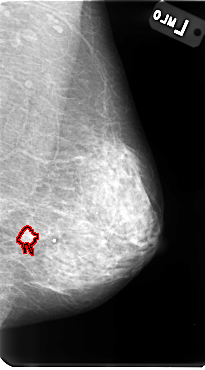

B_3085_1.RIGHT_MLO

LEFT_MLO LINES 4800 PIXELS_PER_LINE 2656 BITS_PER_PIXEL 12 RESOLUTION 50 OVERLAY

FILE: B_3085_1.LEFT_MLO.OVERLAY

TOTAL_ABNORMALITIES 1

ABNORMALITY 1

LESION_TYPE MASS SHAPE IRREGULAR-ARCHITECTURAL_DISTORTION MARGINS SPICULATED

ASSESSMENT 4

SUBTLETY 4

PATHOLOGY MALIGNANT

TOTAL_OUTLINES 1

BOUNDARY